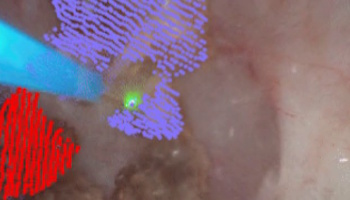

The Advanced Robotics and Controls Lab (ARClab) at UCSD is dedicated to research in design and automation of intelligent robots for the betterment of humanity. Key areas of research are in:

Here's a 3-minute teaser given by Professor Yip for students highlighting active research in the lab (Oct 2023):